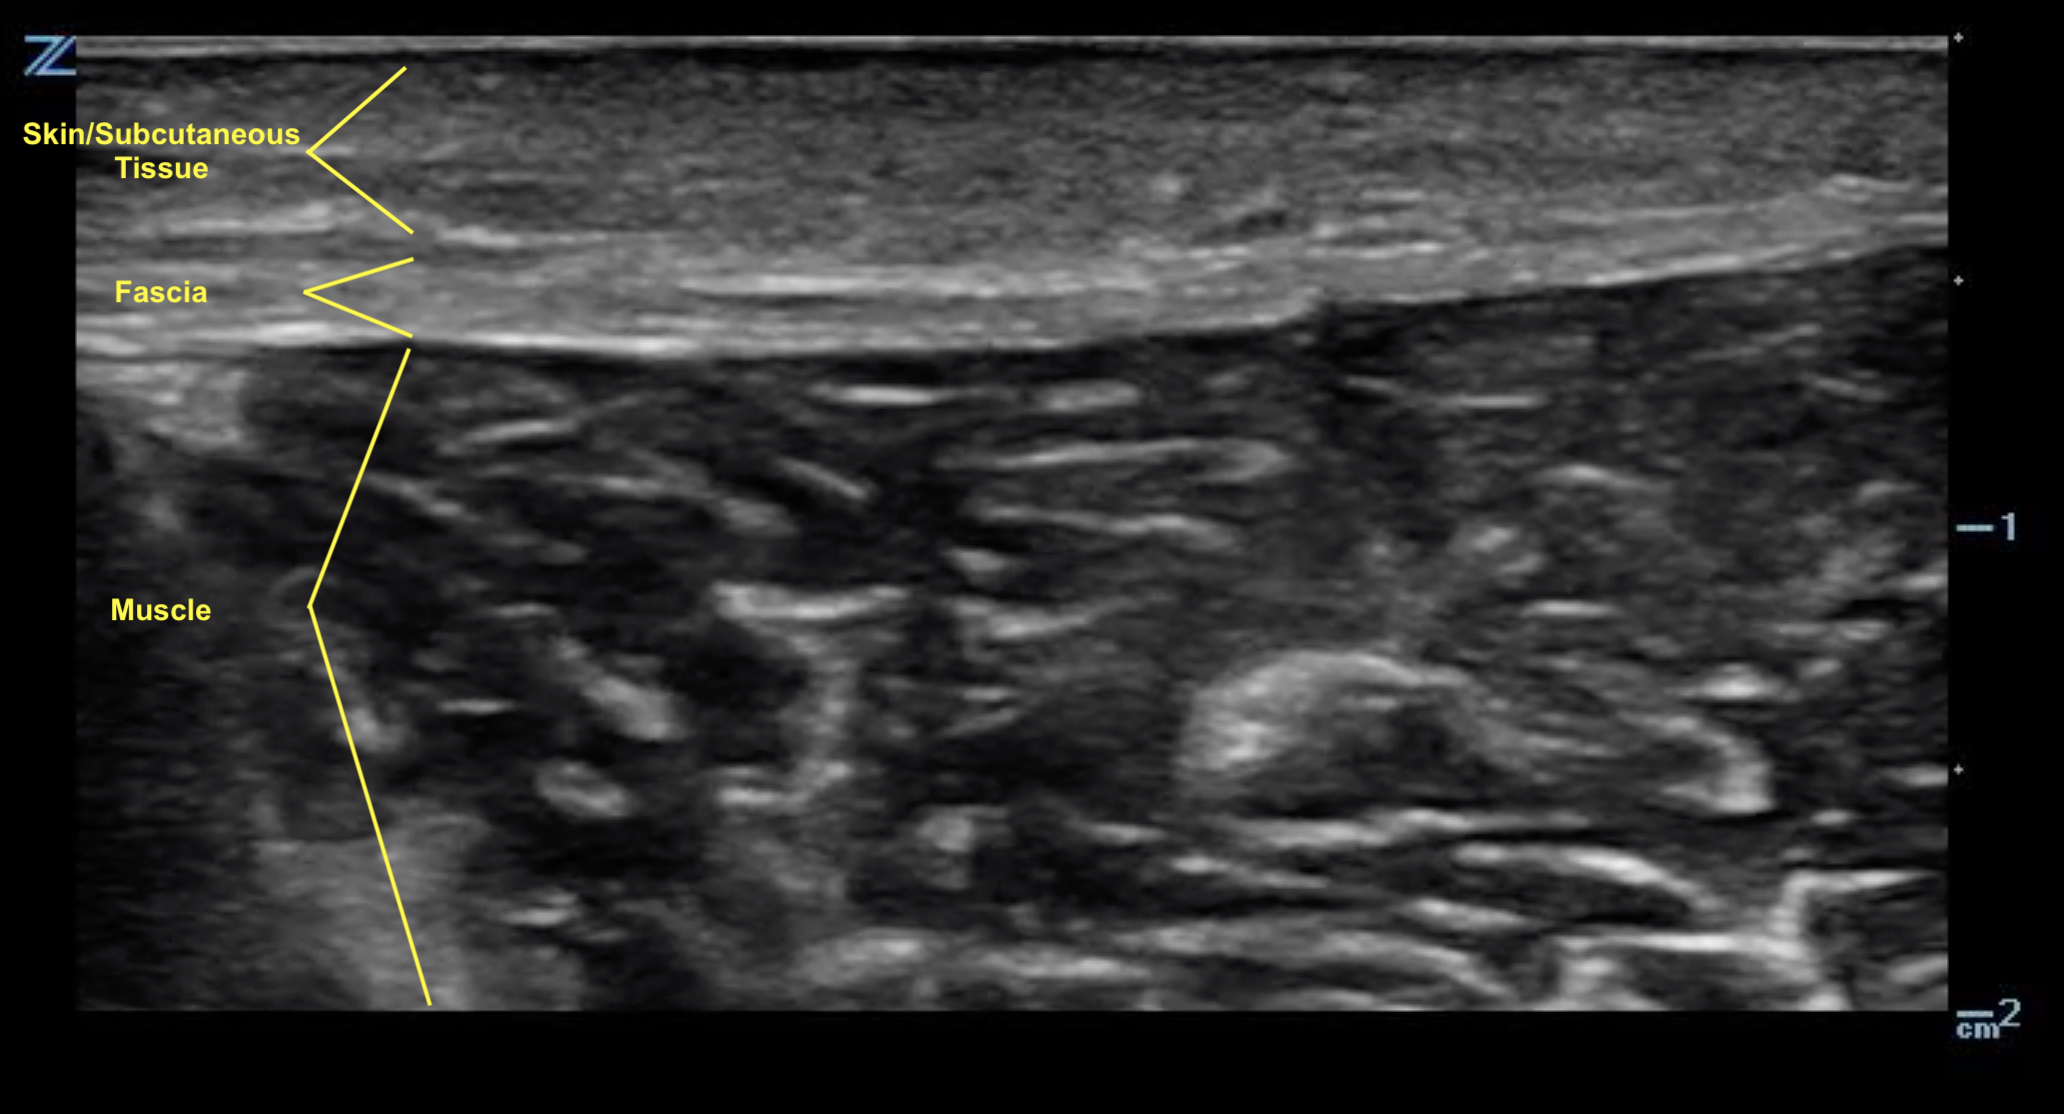

Phlegmon is an area of inflammation in the tissues while an abscess is a little bag of pus that’s more contained The way they’re treated is a different too This article will discuss a. Phlegmon is a medical term describing an inflammation of soft tissue that spreads under the skin or inside the body

It’s usually caused by an infection and produces pus Phlegmon is an area of soft tissue or fluid density effacing or displacing usual fat or other connective tissue and shows variable enhancement However, an abscess typically has a. A phlegmon is a localized area of acute inflammation of the soft tissues

Instead the infection spreads along tissue planes and between muscle fibers. Phlegmon is a serious skin infection that affects the soft tissues, leading to inflammation and a collection of pus It is often caused by bacteria entering the skin through a. This article explores the causes, symptoms, diagnosis, and treatment of phlegmon, including its classifications based on clinical course, severity, location, cause, pathogenesis,.